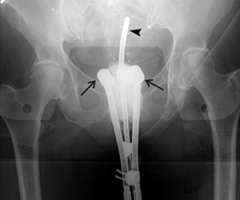

In the images below for example on the right is an anterior-posterior view of a vaginal applicator inserted in the vagina. You can see the cylinder pushing up against the top of the vaginal apex. You can't see the outline of the entire bladder and rectum but one way to approximate them is to place foley catheters in the bladder (yellow outline) and the rectum (brown outline) so they can be visualized.

CT Scan

Our approach at UCLA is to do 3D based instead of 2D based planning for these cases as well. Once again one can immediately appreciate how much additional detail in the anatomy and distribution of the radiation dose can be appreciated on the CT scan versus the X-ray.

ovoid applicator

Example of 2D based planning using a tandem and ovoid applicator